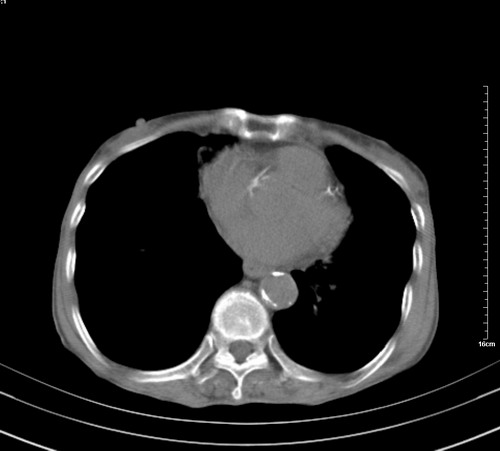

病人,女,79岁,主要因腹疼二月入院,彩超,肝,胆,脾,未见异常,胸透上消化道造影未见异常,化验白细胞增高,内科医生让做胸部ct检查,因为熟人多做了腹部(外科会诊考虑胆囊炎).现ct片如下请假各位战友.

中后纵隔占位,气管、食道受压、变形、移位。恶性可能性大。

考虑:中后纵隔转移瘤可能性大,主动脉硬化。

1 气管旁、隆突下淋巴结明显肿大,肝左叶外侧段低密影,都考虑转移。

纵隔淋巴结肿大,考虑转移而来

肺癌,纵隔淋巴结转移,肝左叶病变考虑为转移病灶。

后中纵隔团块影,伴气管、食道受压移位,首先考虑转移瘤,肝s5段低密度灶。建议增强检查,另外其结肠是否有问题请提供,右肺部分肺叶局限含气增多,考虑局限肺气肿。

建议强化检查,考虑纵隔型肺癌,小细胞可能性大。

后中纵隔团块影,伴气管、食道受压移位,首先考虑转移瘤,肝表现同11773。

后中纵隔淋巴结肿大,首先考虑转移瘤。